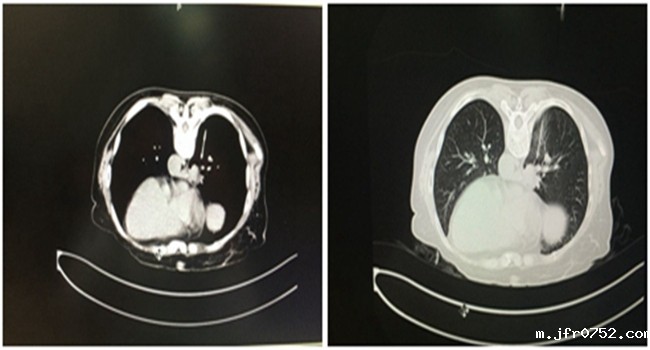

某患者于2016-04-19就诊我科,依据PET-CT检查,拟诊“右肺癌 多发骨转移癌”,患者剧烈疼痛,严重影响日常生活。在北京就诊半月余,因肺部肿块位置非常特殊,上面是下腔...